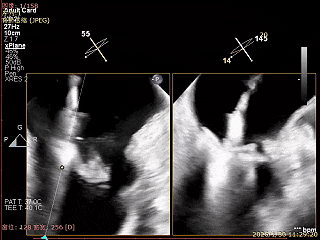

捕捞瓣叶,确定瓣叶瓣尖稳定插入夹臂后,Gripper Down

Gripper Down后Bouncing明显

夹子关紧后,前后叶受限明显

夹子内侧反流消失

夹子外侧残余脱垂与反流

关紧后,前后叶受限明显

夹子释放后,反流基本消失

LVOT切面可见主瓣二尖瓣术后反流基本消失

植入两枚夹子后二尖瓣平均跨瓣压差2mmHg